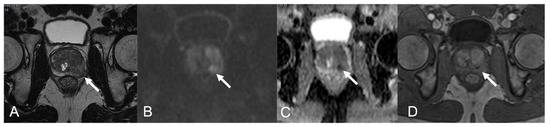

| 1 | PZpm mid-left; TZa mid-base right | 2-cm hypointense PZ nodule; 1.5-cm marker hypointense irregular TZ lesion | Isointense nodule; Slightly hyperintense | Marked low ADC value; Low ADC value | Peripheral rim enhancement and avascular core; Inhomogeneous, early and prolonged hyperenhancement | 4; 5 |

| 2 | PZpl mid-left | 2.5-cm hypointense nodule, capsular bulging | Hyperintense | Low ADC value | Thick peripheral rim enhancement, avascular core | 4 |